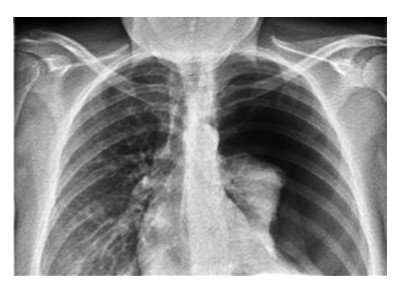

Spontaneous pneumothorax is a common clinical condition in respiratory medicine, typically managed through either conservative measures or pleural drainage. One of the recognized complications following drainage is re-expansion pulmonary edema (REPE), which is usually mild and self-limiting. However, in rare instances, REPE can manifest severely. This report describes a case of unilateral severe REPE that developed shortly after pleural drainage for a spontaneous pneumothorax, complicated by extensive pulmonary plasma leakage. The patient experienced a sudden and critical decline in both respiratory and circulatory status. Emergency management included prone and head-down positioning to optimize ventilationperfusion matching, aggressive fluid resuscitation, and initiation of mechanical ventilation. This clinical course highlights the potential for REPE to progress rapidly to life-threatening respiratory and hemodynamic failure. Clinicians should maintain a high index of suspicion for severe pulmonary re-expansion edema in patients who deteriorate shortly after seemingly successful pleural decompression. Early recognition and supportive interventions are vital for improving outcomes in such critical presentations. In this case report, we discuss such a challenging case, its management and further course we learnt to support our readers.